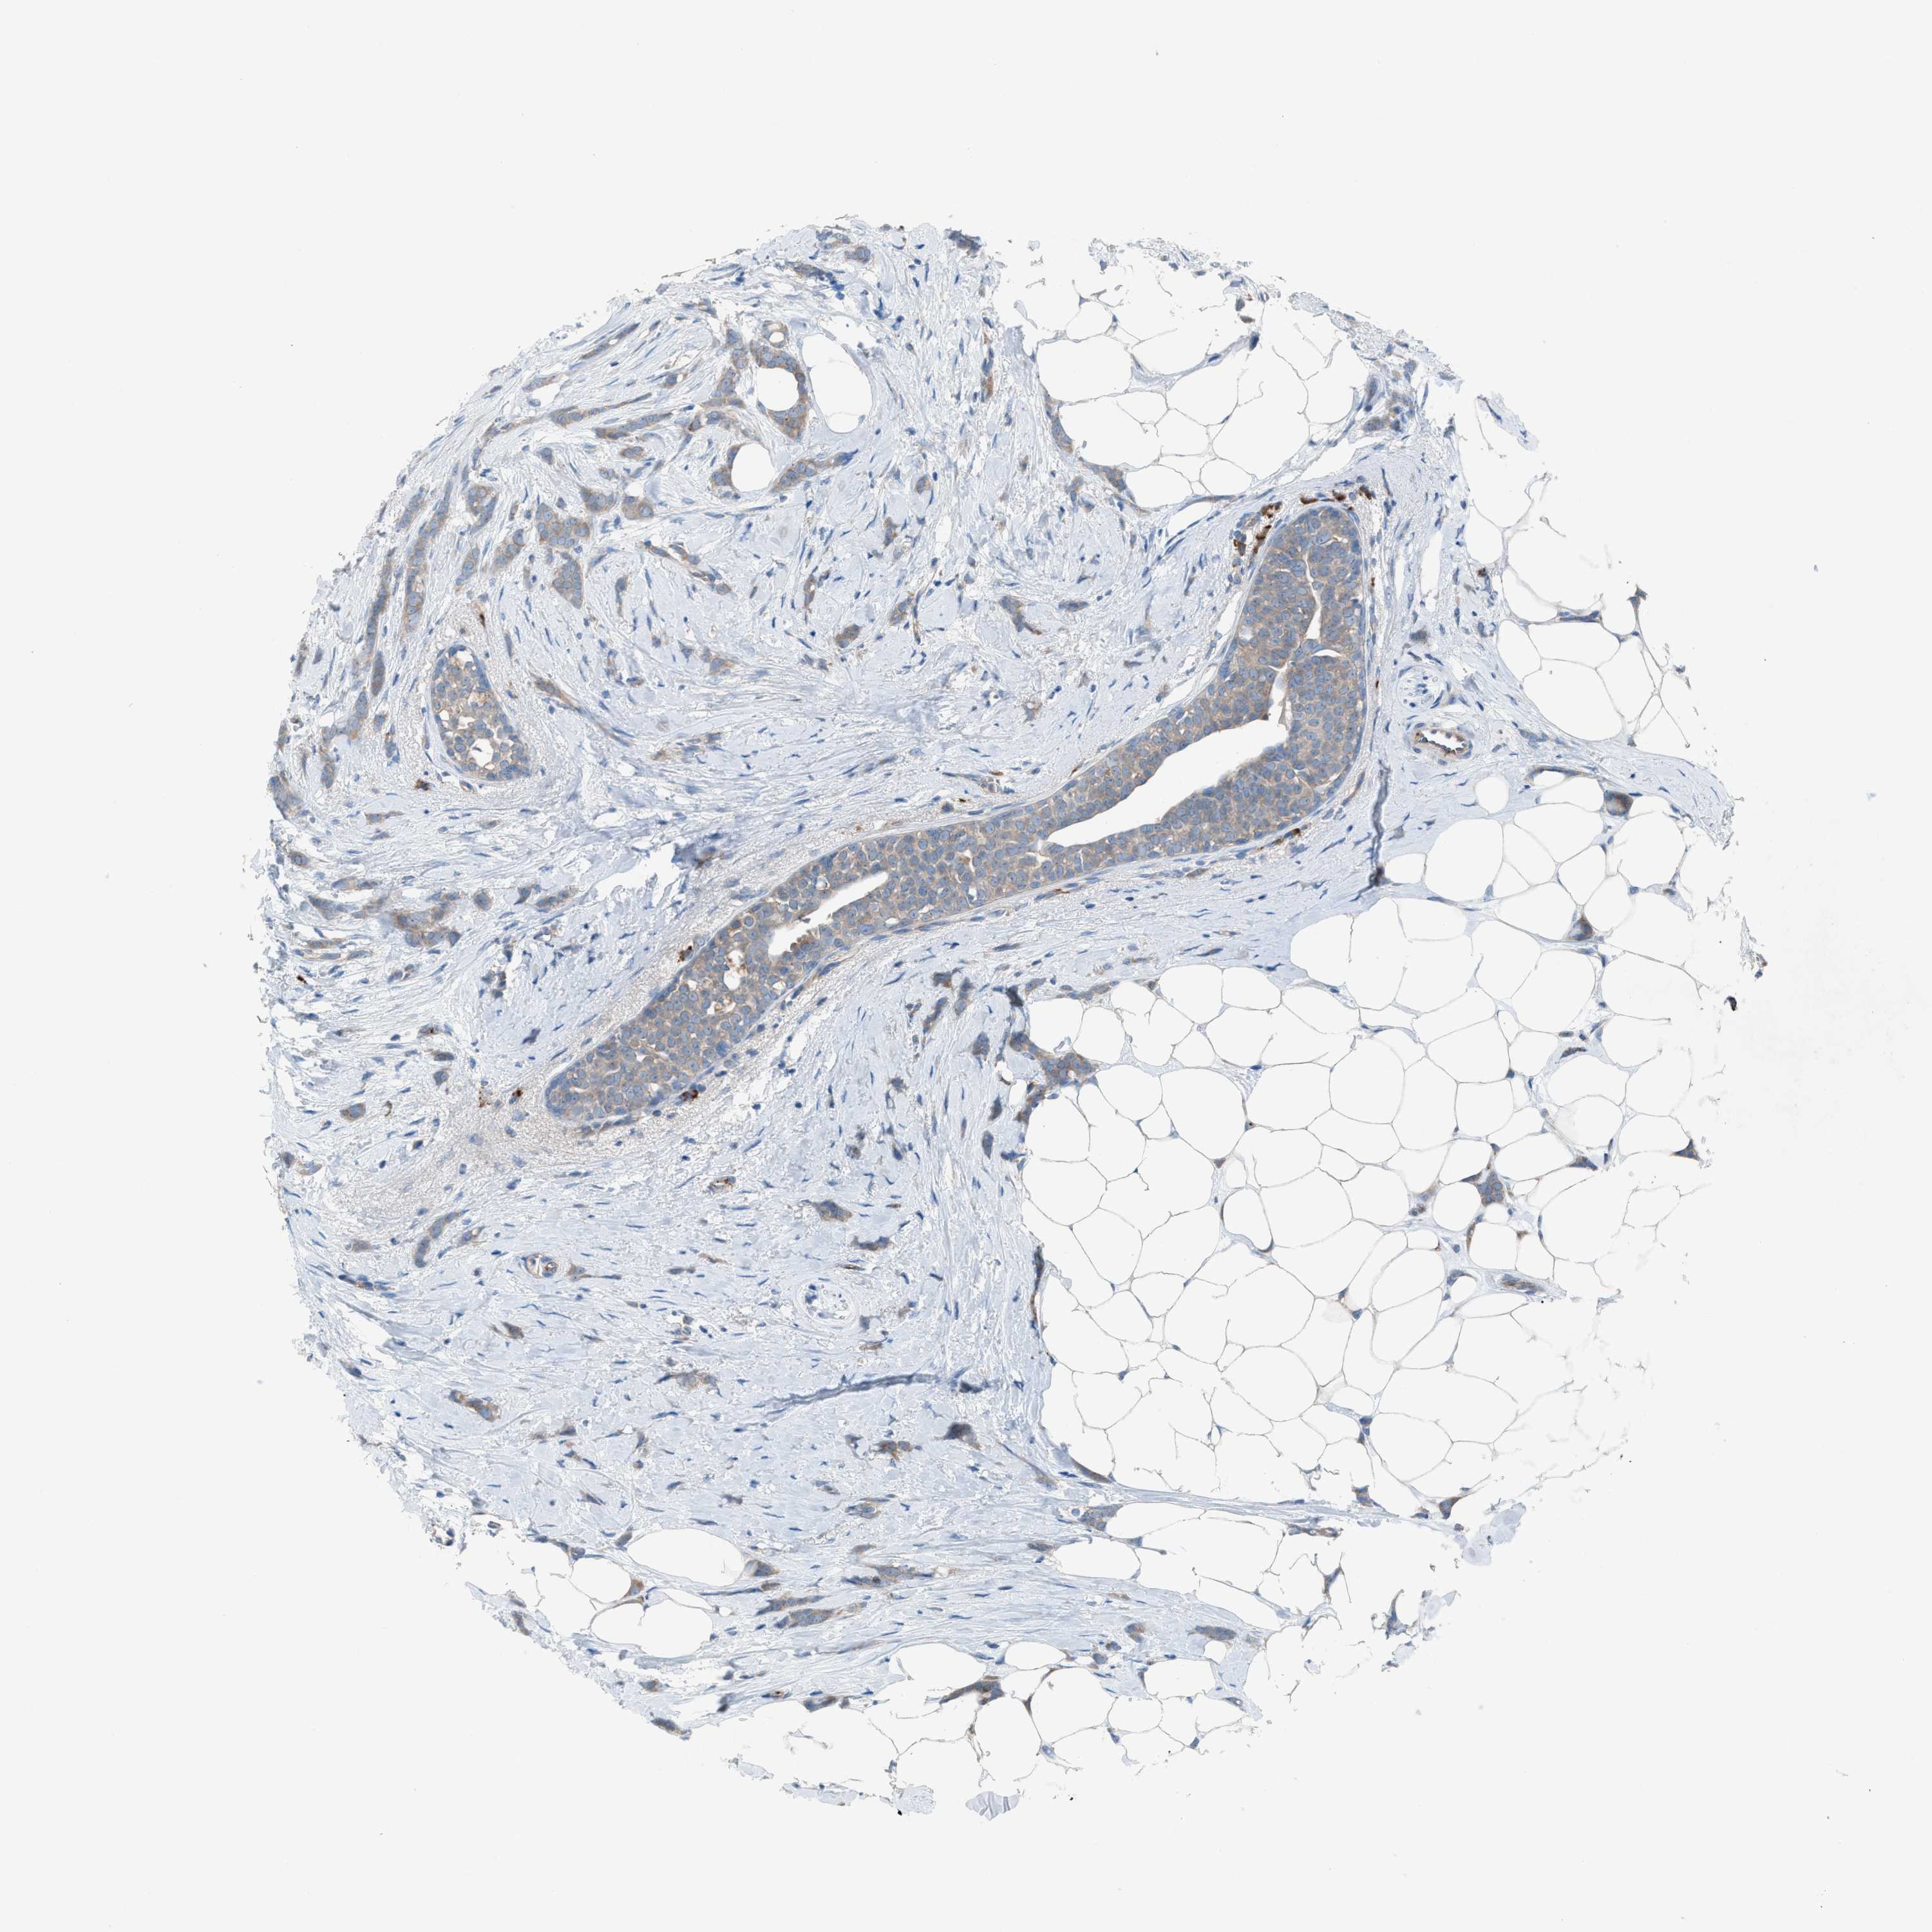

BRCA TCGA BRCA VALIDATION PROTEIN EXPRESSION

ANTIBODIES

AND

VALIDATION